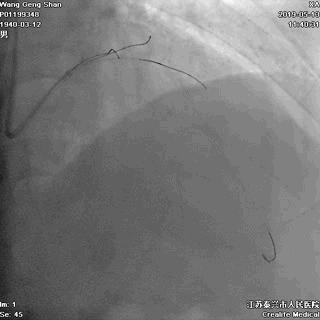

05 LM-LAD支架植入

右头位定位

蜘蛛位定位

LCX球囊拘禁,主支支架释放

回撤LCX球囊

支架球囊再次扩张支架